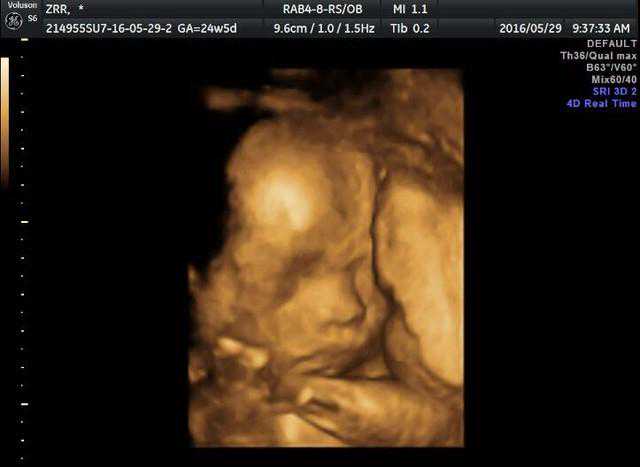

孕期需要采用阴式B超筛查?它是否伤身?医生:这3类孕妇,建议做

“孕期”对女性而言是一生中非常特殊的阶段,短短几个月的时间,...